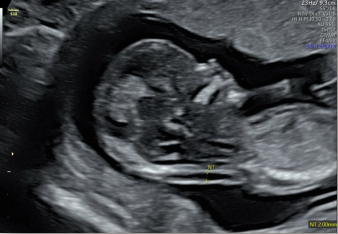

生長指標(biāo)半自動(dòng)測量

在合適切面下,可自動(dòng)識(shí)別測量臨床所需的胎兒雙頂徑,頭圍,腹圍,股骨長和肱骨長度等多個(gè)參數(shù)。